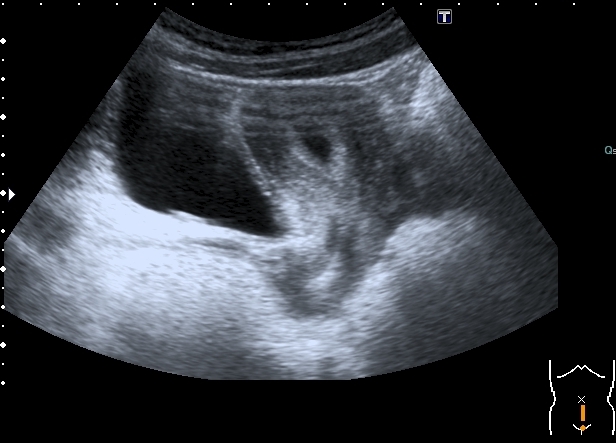

Девочка 14 лет, в течение последних нескольких дней циркулирует между хирургическим и нефрологическим отделением в связи с болями в животе, изменениями в анализах мочи,дизурическими явлениями.

На УЗИ:

Увеличенная матка с анэхогенным содержимым в полости